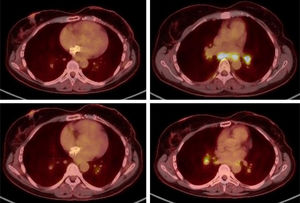

In February 2024, a PET/CT scan was requested to monitor the oncological disease, visualising multiple hiliomediastinal lymphadenopathies, with a characteristic pattern of granulomatous inflammatory disease (Fig. 1). A bronchoscopy was performed with a biopsy of these adenopathies, with an anatomopathological finding of non-necrotising granulomatous lymphadenitis (Fig. 2), confirming the diagnosis of sarcoidosis.

The patient was asymptomatic and without any clinical repercussions at the pulmonary level, with normal respiratory function in tests, while also maintaining good oxygen saturation. For this reason, treatment with capecitabine was continued and active follow-up was carried out without any other additional treatment measures. A follow-up PET/CT scan run at 2 months showed an overall decrease in the intensity of uptake of hiliomediastinal adenopathies.

The only symptomatology presented by the patient in the following months was plantar toxicity. In September 2024, elevation of tumour markers was detected, and tumour progression was confirmed in the PET/CT scan run in October 2024, thus capecitabine was suspended. In this same test, total resolution of the hiliomediastinal lymphadenopathies described above was observed.